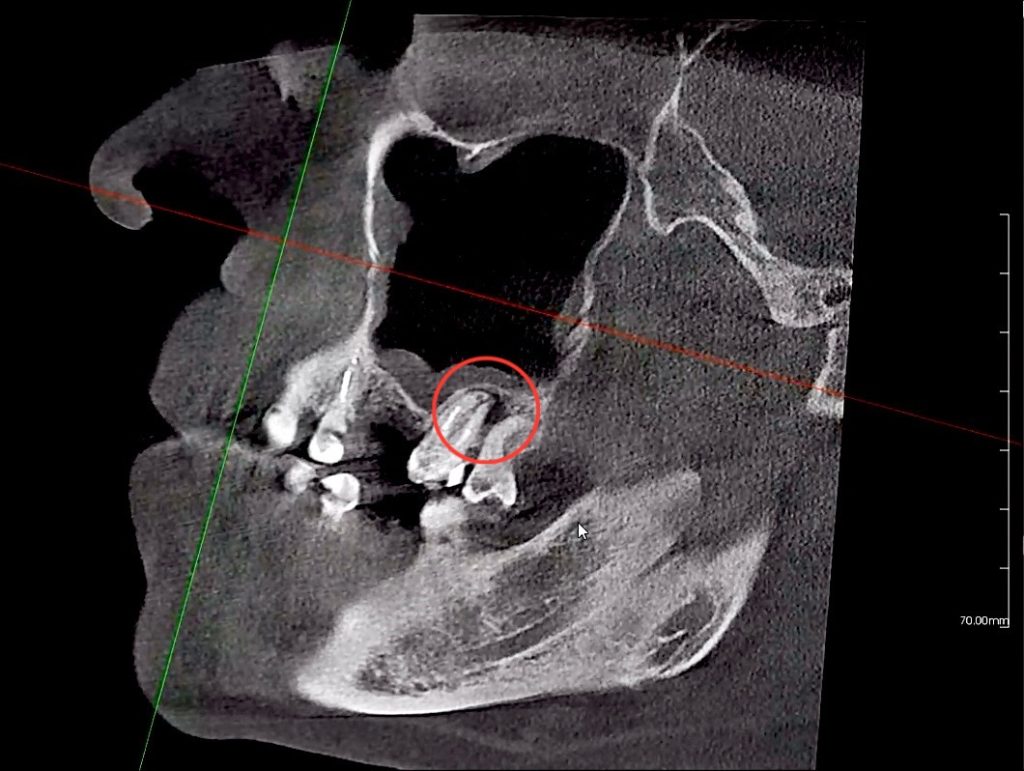

Она формируется как защитная реакция организма на инфекцию и представляет собой полость с жидкостью, окружённую плотной оболочкой. На ранних стадиях киста может никак себя не проявлять и обнаруживается только на рентгеновском снимке.

Хирургическое удаление кисты (резекция верхушки корня).

Через небольшой доступ врач удаляет кисту и инфицированную часть корня, сохраняя зуб. -